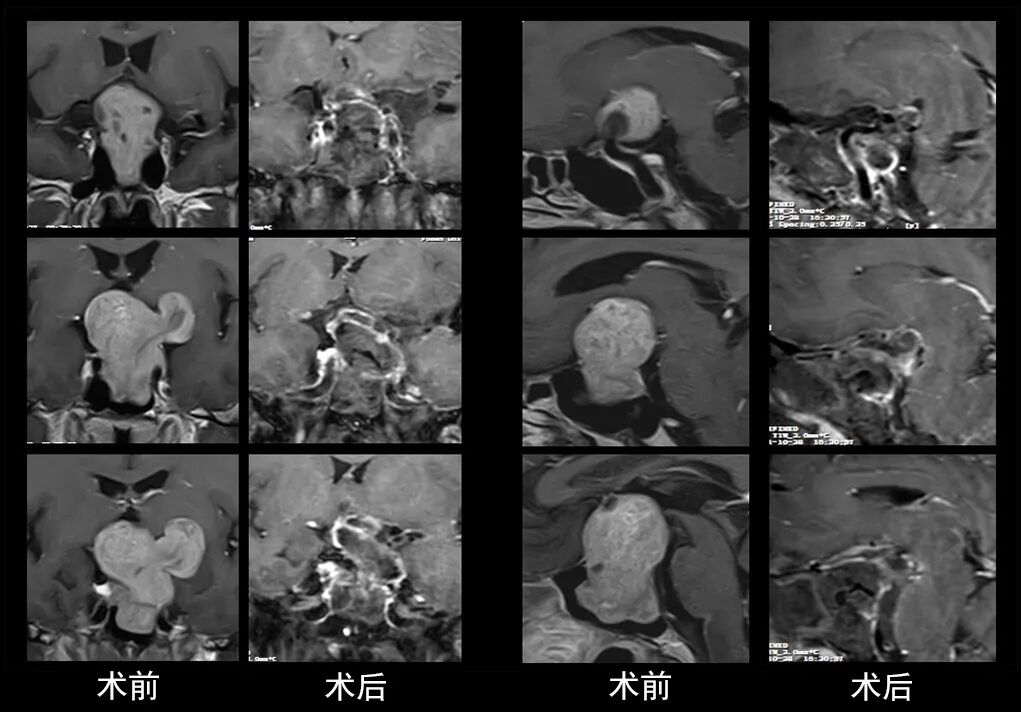

本研究中采用联合手术策略的代表性病例展示:

case 3

case 4